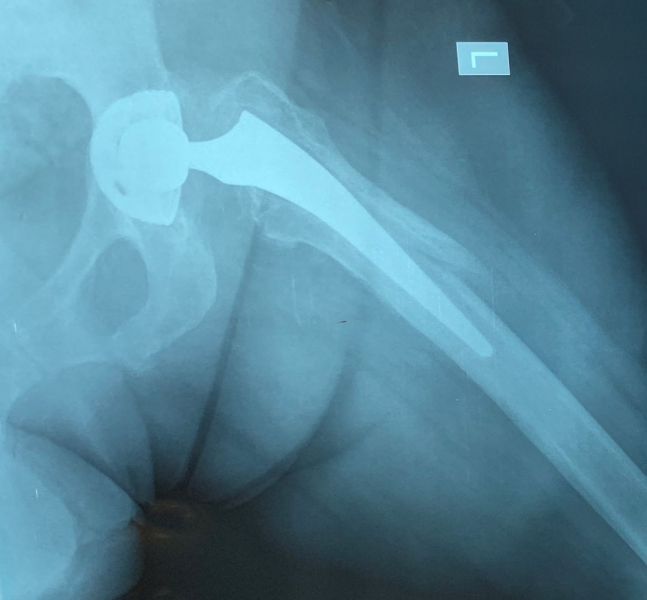

2. Intracapsular fracture of the right hip in a 74-year-old female.

Treatment: Total hip arthroplasty

I. Anteroposterior x-ray pelvis shows the fracture on the right hip II. Anteroposterior x-ray pelvis shows the total hip arthroplasty three months down the line from the operation III. Lateral view hip shows the total hip arthroplasty three months down the line from the surgery